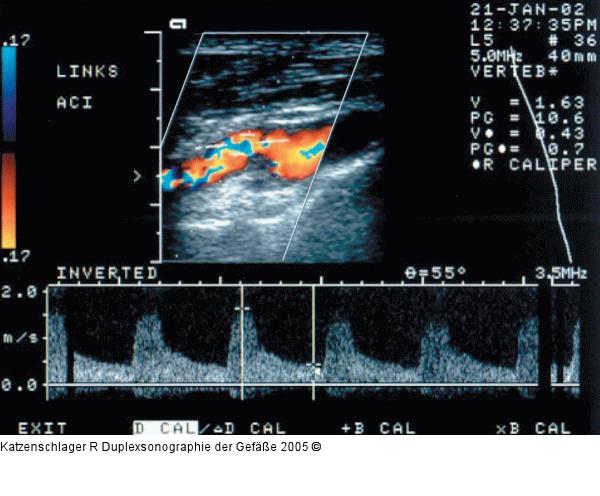

Abbildung 7b: Duplexsonographie - Karotis Plaque, die die ACI links 50–69 % stenosiert (Vmax 1,6/0,4 m/sec) |

Abbildung 7b: Duplexsonographie - Karotis

Plaque, die die ACI links 50–69 % stenosiert (Vmax 1,6/0,4 m/sec) |